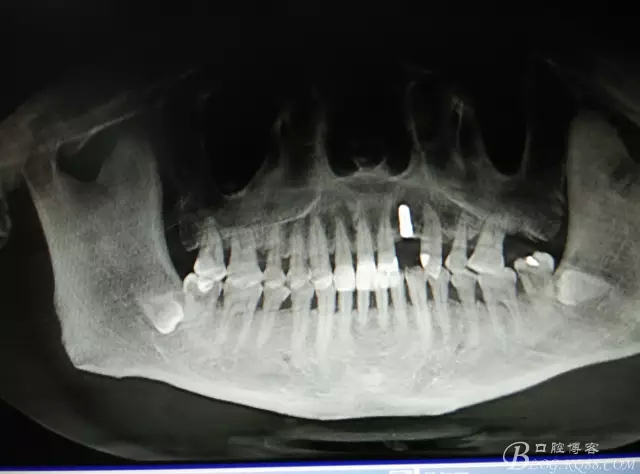

患者、楊xx、男、49歲。主訴:左側(cè)前牙拔除半年,活動義齒修復(fù)四個(gè)月,要求種植修復(fù)。??茩z查:21缺失,牙槽粘膜厚度正常。CBCT檢查:高度16mm,寬度7mm.術(shù)前簽知情同意書。

圖1.術(shù)前的CBCT檢查:22缺失。